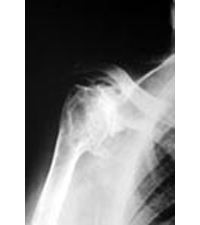

La artrosis glenohumeral es la enfermedad degenerativa de la articulación entre la cabeza humeral y la cavidad glenoidea del omóplato, en la que se produce una pérdida del cartílago que recubre las superficies articulares con desaparición del espacio articular, así como un endurecimientode las superficies óseas con formación de osteofitos (crecimiento óseo en la periferia de la articulación).

La articulación acromioclavicular es la articulación que une el acromion con la punta de la clavícula. Se trata de una causa frecuente de hombro doloroso.